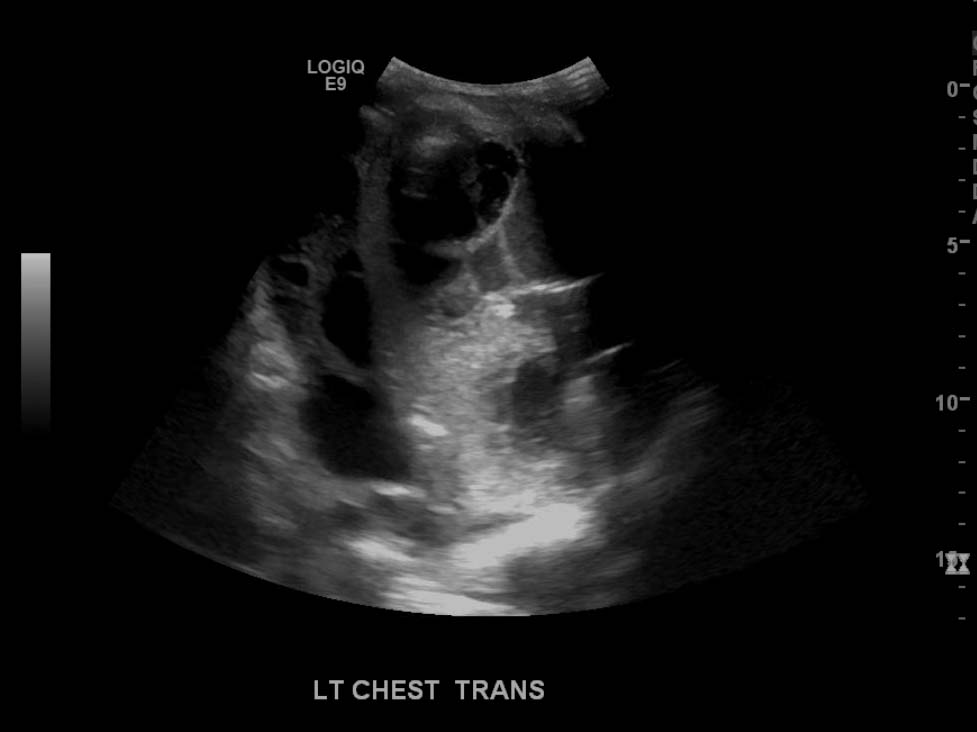

- Large, complex, multiseptated left pleural fluid collection

- Adjacent airspace consolidation in the left lung with air bronchograms

Large, complex, multiseptated left pleural fluid collection with adjacent airspace consolidation, concerning for pneumonia and empyema. No discernible right pleural effusion.

- Worry about a complicated effusion (which may represent empyema, hemothorax, or malignant effusion depending on the clinical scenario) if the fluid collection has hyperechoic areas or if it contains internal septations

- Also, when densely consolidated, the lung becomes more discretely visible and takes a liver-like appearance, referred to as “hepatization”